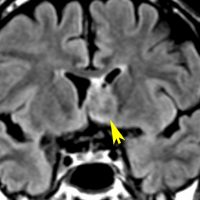

全く何もしなくても良い成人の毛様細胞性星細胞腫

20代女性に偶然発見された視床下部(第3脳室)腫瘍です,T1低信号,T2で高信号,右側のガドリニウム造影では全く増強されません。毛様細胞性星細胞腫と診断できます。眼科での視野検査で視野欠損はありませんでした。生検術もなにもせず経過をみました。

左が初診時,右が5年後のMRI画像です。腫瘍の大きさは全く同じです。このような腫瘍はしばしば経験します。慌てて生検術や開頭手術など計画しないで,画像診断をしっかりすることが大切です。